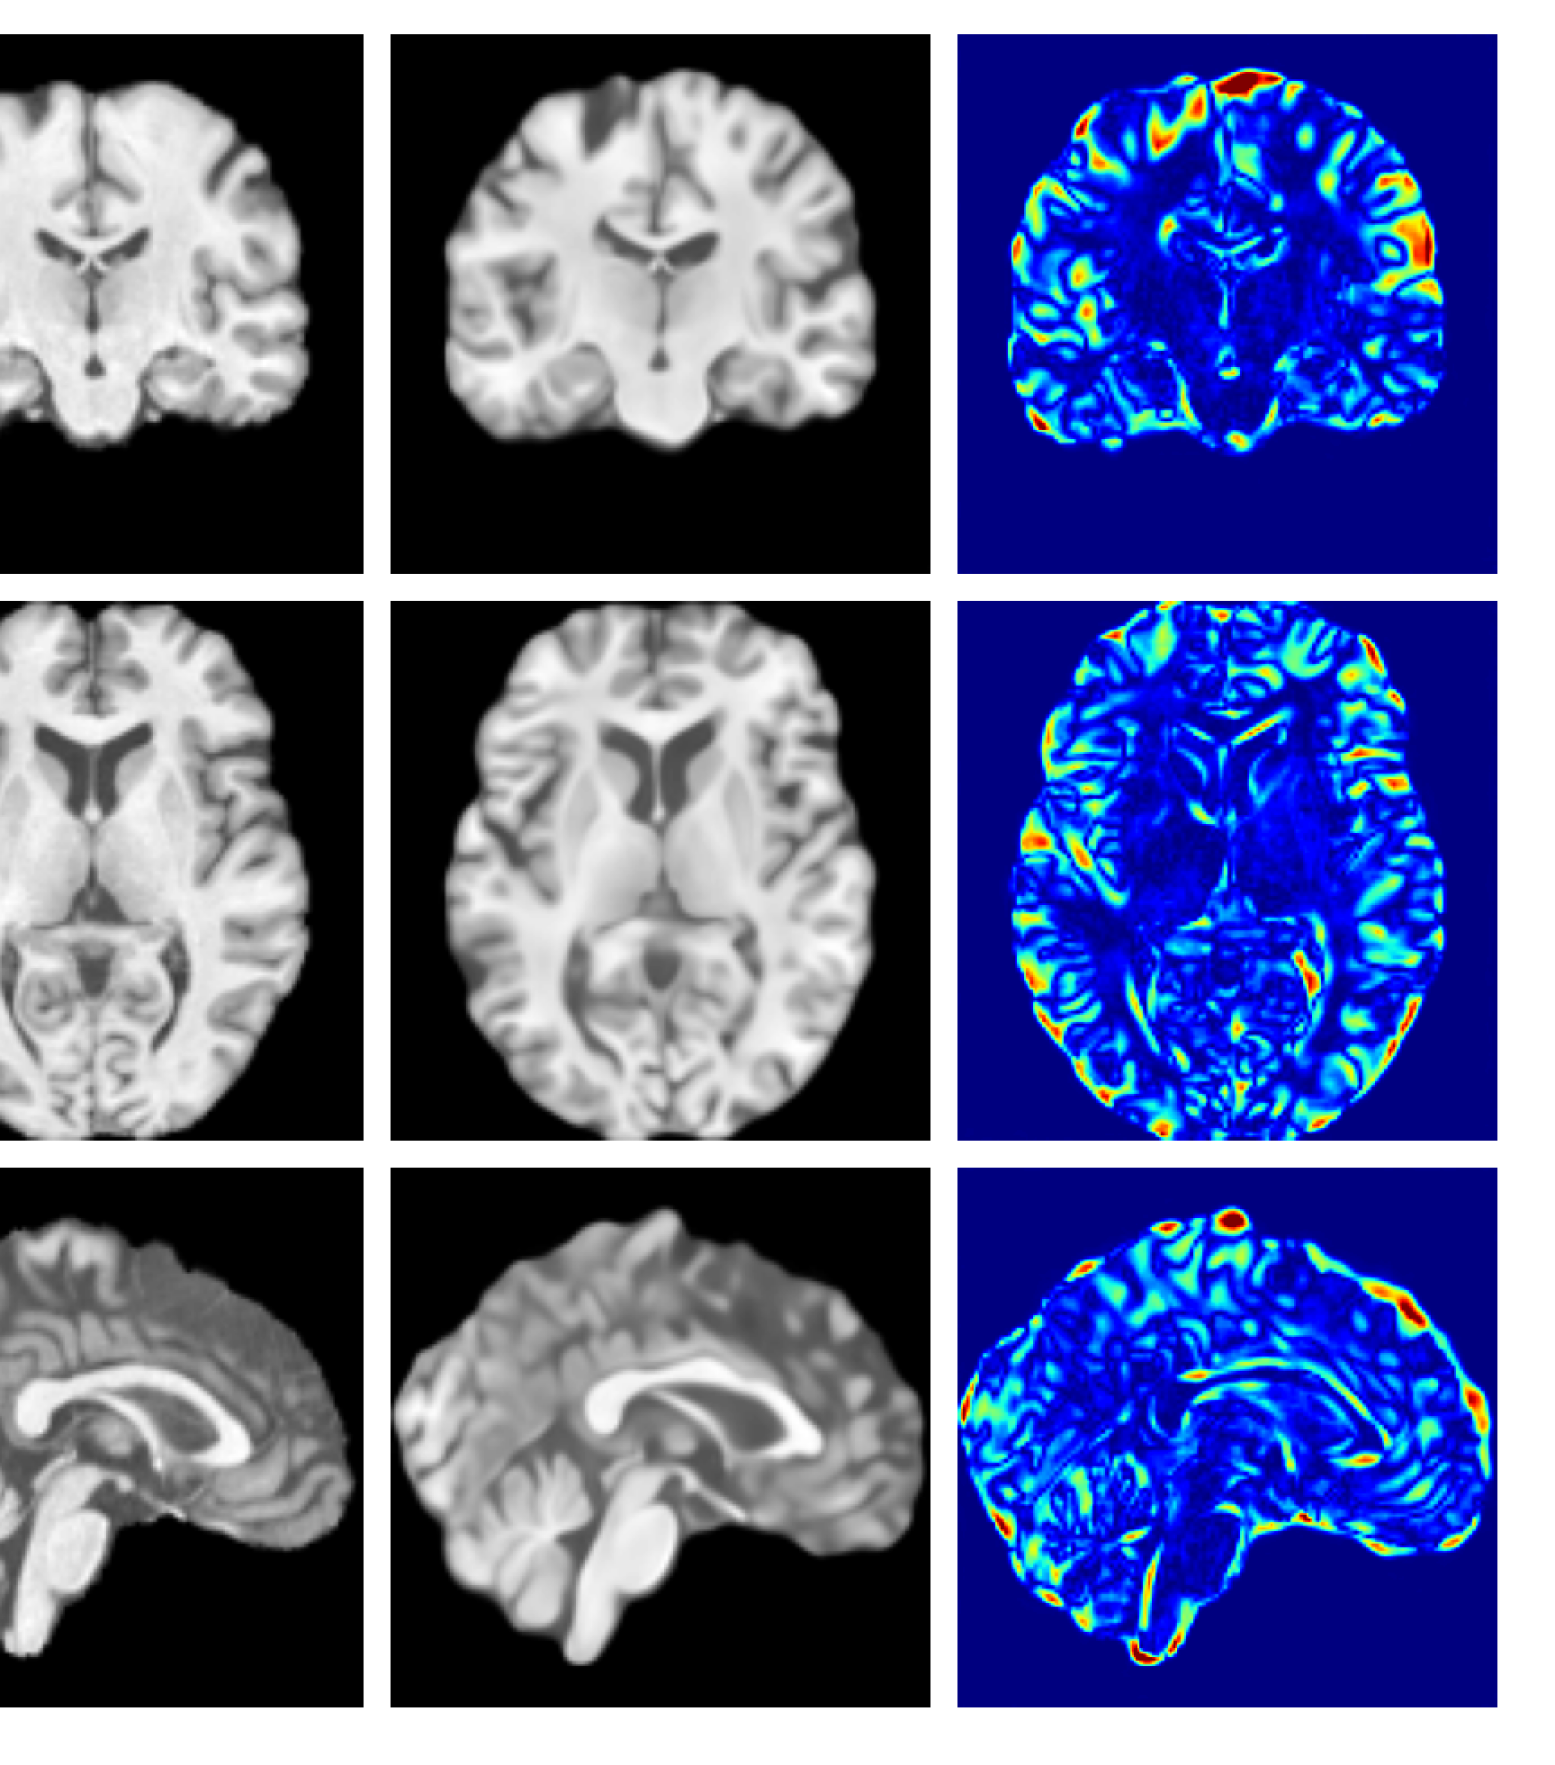

Figure 7 provides example reconstructions and anomaly maps for a healthy subject from the UK Biobank holdout test cohort.

Figure 7: Example healthy reconstructions and anomaly maps for a sample from the UK Biobank healthy test cohort. For a healthy subject, we should observe no regions highlighted in the anomaly map.